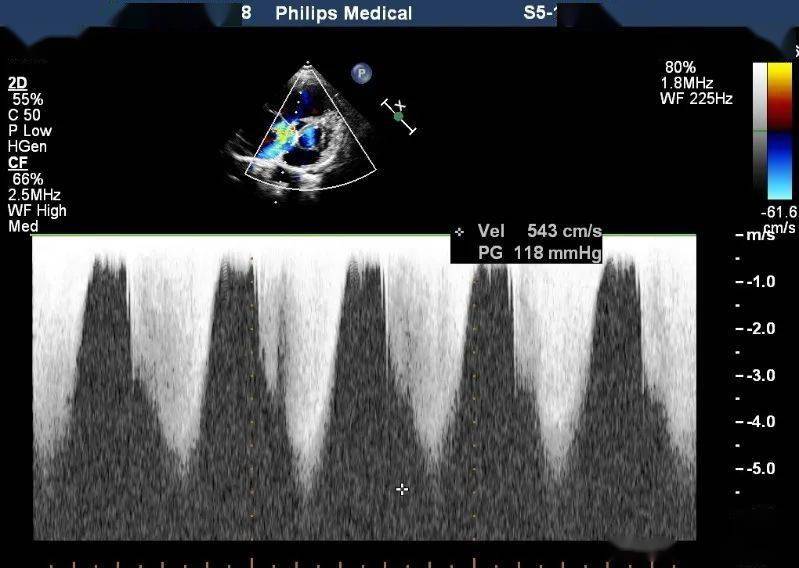

三,肺动脉狭窄 | 超声掌中宝

图片尺寸2400x1800